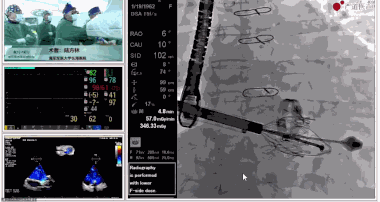

陸方林教授分享的是一例極重度三尖瓣返流的患者采用健世科技(LuX-Valve®)經(jīng)導(dǎo)管三尖瓣置換系統(tǒng)進(jìn)行的手術(shù)直播演示。此例患者為69歲女性,入院前17年行二尖瓣機(jī)械瓣置換術(shù),術(shù)后長(zhǎng)期服用華法林抗凝,既往“2型糖尿病”病史5年,“雙下肢水腫”3年。3個(gè)月前患者出現(xiàn)腹脹、雙下肢水腫,伴活動(dòng)后暈厥,伴黃疽、皮膚濕癢、牙齦出血,癥狀持續(xù)加重,遂入院治療。入院后行心臟CT、心臟超聲檢查,提示:“三尖瓣關(guān)閉不全(極重度),二尖瓣置換術(shù)后,心功能III級(jí)”。徐志云、陸方林微創(chuàng)三尖瓣置換團(tuán)隊(duì)對(duì)該患者的病情進(jìn)行了充分的評(píng)估和討論。由于患者有開胸二尖瓣置換手術(shù)史,且病史時(shí)間長(zhǎng),同時(shí)存在相關(guān)合并癥,傳統(tǒng)外科手術(shù)風(fēng)險(xiǎn)極高(STS評(píng)分:8.315%),最終決定采用三尖瓣LuX-Valve®瓣膜系統(tǒng)對(duì)患者進(jìn)行治療。

圖片

▲術(shù)中食道超聲顯示三尖瓣極重度返流